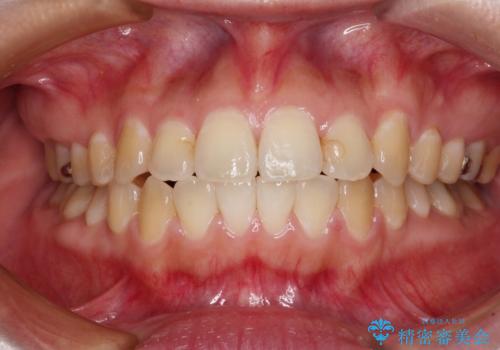

受け口で開咬を急速拡大装置とインビザラインで改善 欠損部分はインプラントにて補綴治療

- 前歯の開咬と、受け口による咬み合わせの悪さを気にして来院された患者様です。

左上は後続永久歯の欠損によりスペースがあり、矯正治療と並行してインプラントあるいはブリッジによる補綴治療が必要な状況でした。

上顎歯列が狭窄していたため、急速拡大装置により上顎骨を側方に拡大し、その後インビザラインにて矯正治療を行うこととしました。